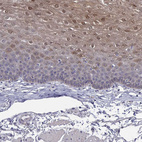

Immunohistochemical staining of human esophagus shows weak to moderate nuclear and cytoplasmic positivity in squamous epithelial cells.